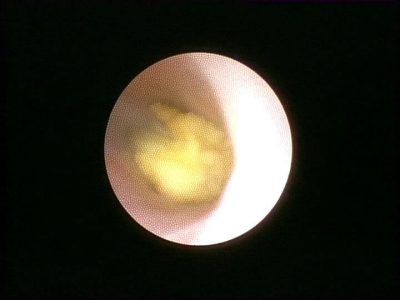

Başta tükürük bezi taşları olmak üzere,tükürük kanallarını tıkayan hastalıkların teşhis ve tedavisi, günümüzde sialendoskopi yöntemi ...